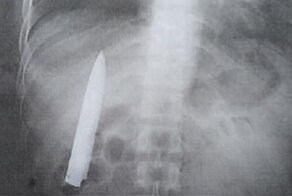

Старинный многолезвийный нож китайских врачей

Впрочем, у врачей и у маньяков инструментарий одинаково пугающий, так что очень может быть))

Пианино настраивается с помощью камертона. В верхней части справа от длинного лезвия.